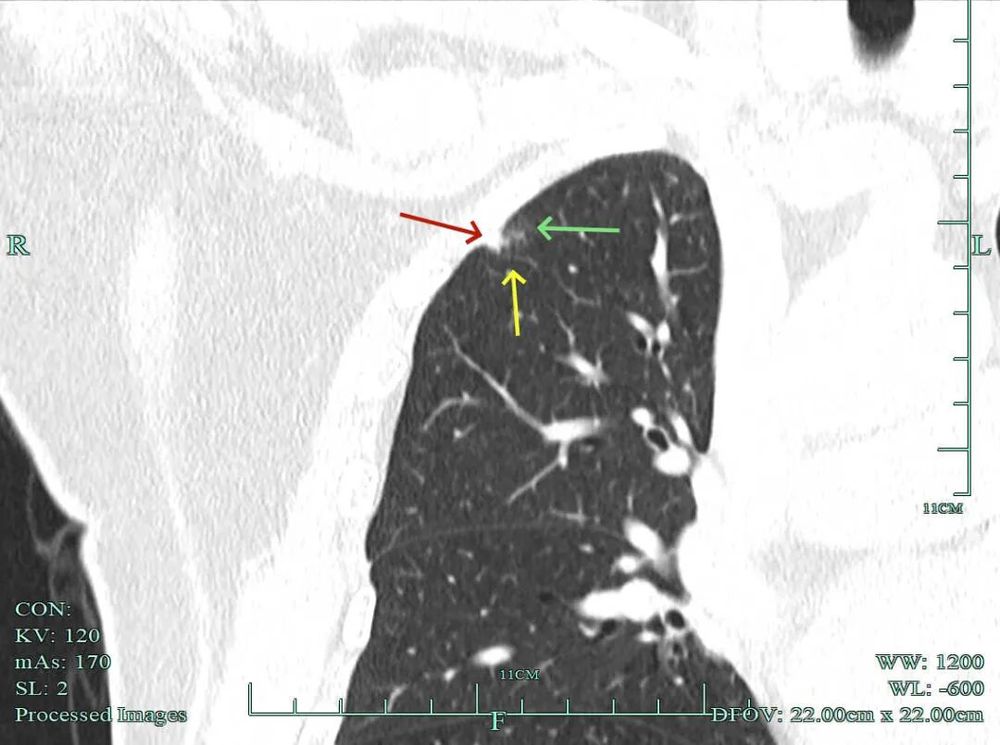

影像展示与分析:

杭州市肿瘤医院影像展示与分析:

右上也有混合密度结节,实性部分缺乏膨胀性与收缩力,磨玻璃成分较淡,也偏糊,但持续存在仍得考虑肿瘤范畴可能性大。

此视角是混合密度,实性为主,贴胸膜近。

今天这位结友的病理类型稍差于术前的预测,但从其三年多随访情况来看,进展不算大厉害,第10组与第12组淋巴结均阴性的话,还是真早期的可能性还是较大的。后续倾向暂随访观察,可以采取相对稍积极的随访策略,比如两年内4个月复查一次,三到五年内半年复查一次,五年后再年度复查;而且右侧的病灶要在随访进展或身体恢复良好后微创局部楔形切除。期间万一有转移,其实是伪早期的话,则基因检测并全身性治疗。其实今天这种病灶在临床中被判断为炎性的并不少见,尤其是非胸外科医生。因为胸外科的一般相对积极,警惕性高些。在我的公众号上其实也分享过多例这种看着似乎是炎性,但长时间随访不好转,或缓慢进展的病灶其实是浸润性腺癌的一种特殊表现,不少见的。我感觉此类病灶比较主要的临床特征是:1、密度多是混合磨玻璃密度,实性成分较明显,磨玻璃成分较淡,病灶显得密度较为杂乱不均;2、整体形态膨胀性不明显,收缩力不太强;3、灶内支气管通气及显得较为僵硬,血管征不典型,但表面多是不平不规则,较为毛糙,分叶多可见;4、随访或抗炎治疗不好转,进展不快,相对较为缓慢。容易被人以为是慢性炎症。但此时我们要注意几点:1、寻找磨玻璃成分,并观察瘤肺边界,尤其是磨玻璃成分与周围正常肺组织之间的界限是否清楚,清楚的多是恶性;2、靶重建从不同角度观察病灶形态,看病灶与邻近结构的关系,有无推压、破坏或支气管截断等征象;3观察病灶内部通气支气管的形态,扭曲、僵硬不舒展的多容易是恶性病变。总体上,要对“影像看着像慢性炎,但随访持续存在且有磨玻璃成分的”病灶要特别提高警惕,对于靠近边缘部分的,手术创伤不大的,要考虑“开刀带来创伤与随访导致的风险”之间的利弊权衡。我的根本理念仍是:淡化最后病理结果,从风险角度考虑问题!